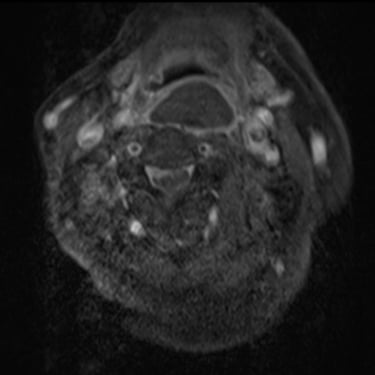

Discitis Cervical con Absceso: Descompresión Cervical y Artrodesis

La discitis cervical con absceso es una infección grave de la columna que puede comprometer el disco intervertebral, los cuerpos vertebrales y las estructuras neurológicas, generando dolor cervical intenso, fiebre y déficit neurológico progresivo. Cuando existe compresión medular o inestabilidad, el tratamiento quirúrgico mediante descompresión cervical y artrodesis es fundamental. Este procedimiento permite drenar el absceso, liberar la médula espinal y estabilizar el segmento afectado, favoreciendo el control de la infección y la recuperación neurológica. El manejo oportuno y multidisciplinario es clave para mejorar el pronóstico del paciente.